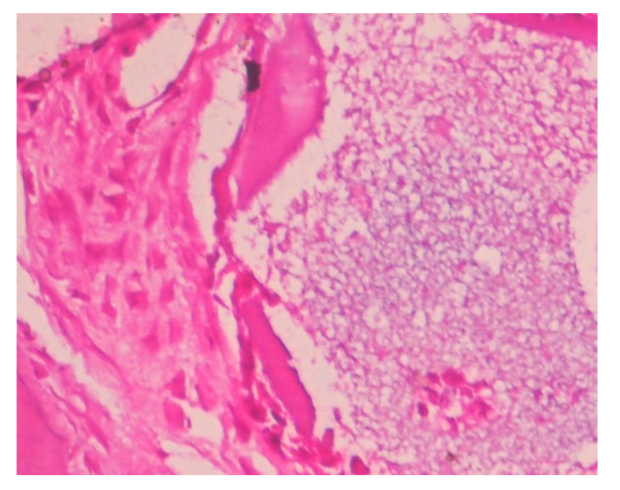

Biopsies were fixed in 10% formalin, decalcified with 0.5M EDTA, and sectioned. Hematoxylin and eosin (HE), Van Geison, Mason trichrome and Picrosirius Red were used. Microscopic analysis revealed remnants of dentin particles integrated with new lamellar bone. Plump osteoblasts, entrapped osteocytes, and fibrovascular stroma with minimal chronic inflammation were evident, confirming osteoconductive and osteoinductive potential. Mature bone trabeculae along with residul graft material were confirmed with various special stains.